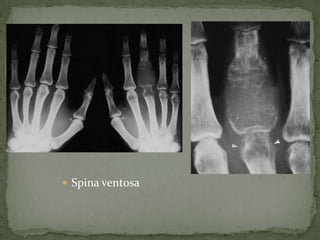

The radiographic features –

 Cystic expansion of the short tubular bones have led to the

name of "spina ventosa" being given to tubercular dactylitis

of the short bones of the hand.

 spina - short bone and

 ventosa - expanded with air

 Bone destruction and fusiform expansion of the bone

 It is most marked in diaphysis of metacarpals and metatarsals

in children

 Periosteal reaction and sequestra are uncommon.

 Healing is gradual by sclerosis.

 Spina ventosa

Tuberculous dactylitis